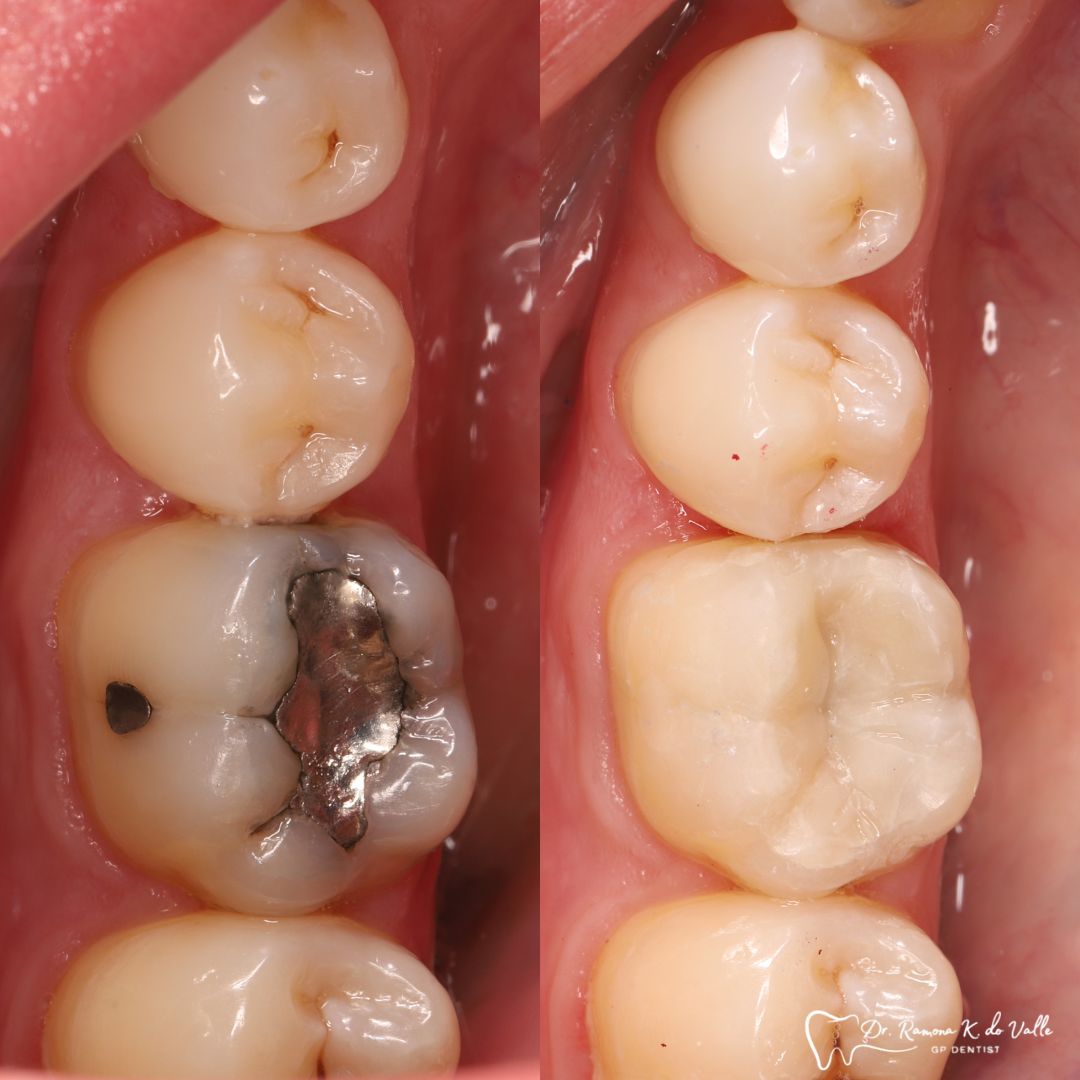

• replacing old metal fillings with a tooth-coloured option

3. Layering the Composite Resin

The tooth-coloured resin is applied in thin layers and shaped carefully to match natural anatomy. For front-tooth work, we may combine several shades for a lifelike result.